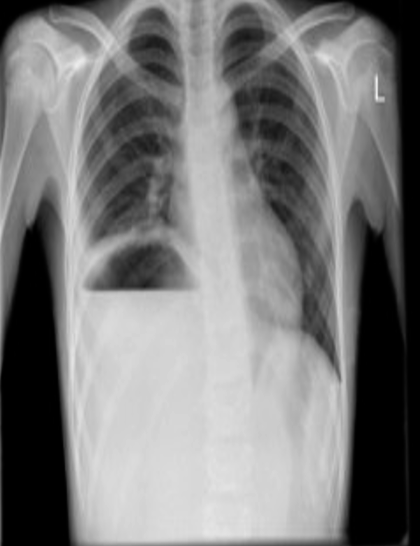

fluid level is seen , the diaphragm is elevated with a subphrenic